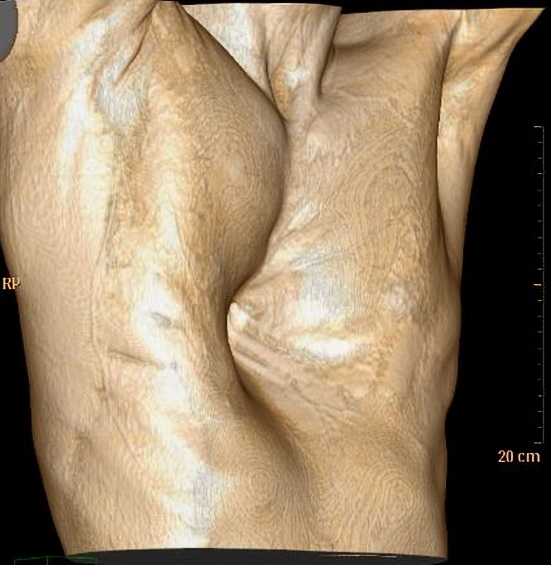

Image macroscopique d'une

syndrome de Poland . Aplasia du muscle

pectoralis majeur gauche et deformation asymetrique

legere du cage thoracique |

Image radiologique TDM en

coupe axial de aplasia du muscle pectoralis majeur

gauche d'une syndrome de Poland |